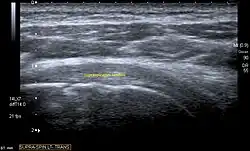

Ultrasound

There are several advantages of ultrasound. It is relatively cheap, does not emit any radiation, is accessible, is capable of visualizing tissue function in real time, and allows the performance of provocative maneuvers in order to replicate the patient’s pain.[28] Those benefits have helped ultrasound become a common initial choice for assessing tendons and soft tissues. Limitations include, for example, the high degree of operator dependence and the inability to define pathologies in bones. One also has to have an extensive anatomical knowledge of the examined region and keep an open mind to normal variations and artifacts created during the scan.[29]

After the introduction of high-frequency transducers in the mid-1980s, ultrasound has become a conventional tool for taking accurate and precise images of the shoulder to support diagnosis.[31][32][33][34][35]

Adequate for the examination are high-resolution, high-frequency transducers with a transmission frequency of 5, 7.5, and 10 MHz. To improve the focus on structures close to the skin an additional "water start-up length" is advisable. During the examination the patient is asked to be seated, the affected arm is then adducted and the elbow is bent to 90 degrees. Slow and cautious passive lateral and/or medial rotations have the effect of being able to visualize different sections of the shoulder. In order to also demonstrate those parts which are hidden under the acromion in the neutral position, a maximum medial rotation with hyperextension behind the back is required.[36]

To avoid the different tendon echogenicities caused by different instrument settings, Middleton compared the tendon’s echogenicity with that of the deltoid muscle, which is still lege artis.[37][38]

Usually the echogenicity compared to the deltoid muscle is homogeneous intensified without dorsal echo extinction. Variability with reduced or intensified[39] echo has also been found in healthy tendons. Bilateral comparison is very helpful when distinguishing and setting boundaries between physiological variants and a possible pathological finding. Degenerative changes at the rotator cuff often are found on both sides of the body.[40] Consequently, unilateral differences rather point to a pathological source and bilateral changes rather to a physiological variation.[38]

In addition, a dynamic examination can help to differentiate between an ultrasound artifact and a real pathology.[41]

To accurately evaluate the echogenicity of an ultrasound, one has to take into account the physical laws of reflection, absorption and dispersion. It is at all times important to acknowledge that the structures in the joint of the shoulder are not aligned in the transversal, coronal or sagittal plane, and that therefore during imaging of the shoulder the transducer head has to be held perpendicularly or parallel to the structures of interest. Otherwise the appearing echogenicity may not be evaluated.[42]